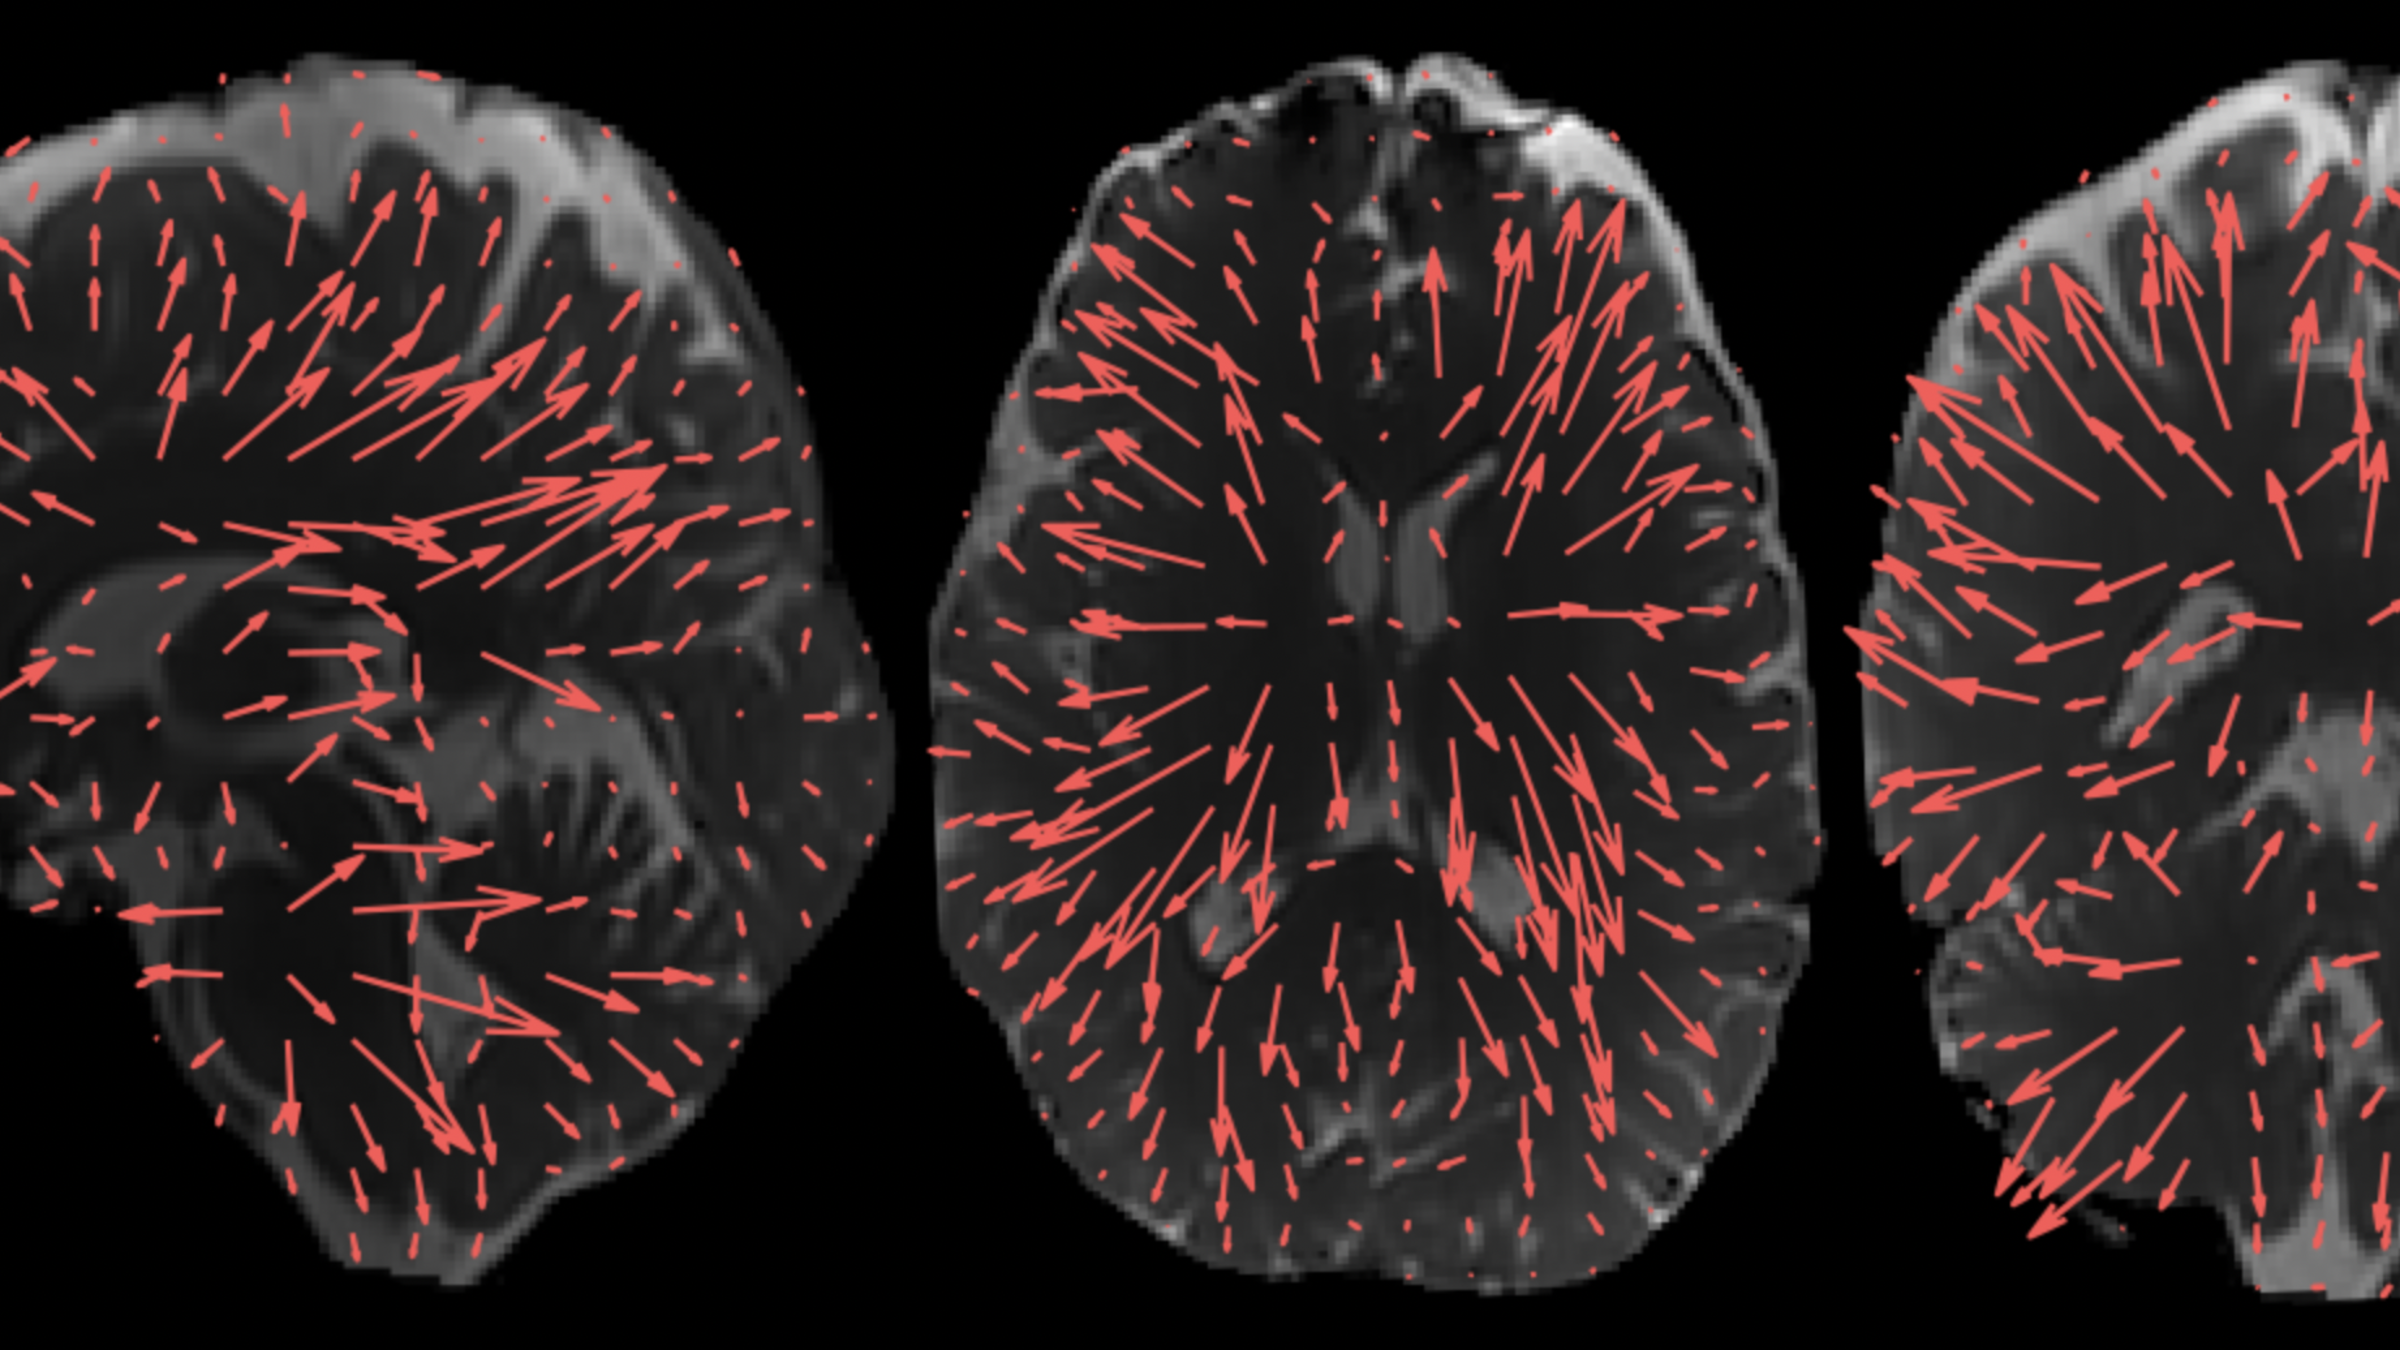

The 3D aMRI method, showing exquisite brain motion that is captured in all three planes of the brain (coronal, axial and sagittal views). Previously amplified motion was only reliably visible in the sagittal plane – the 3D aMRI method now captures motion in all planes. Outlined in Terem et al. Magnetic Resonance in Medicine (2021); Abderezaei et al. Brain Multi-physics (2021). https://youtu.be/bC05R_tcyW4

The arrows show the direction and amplitude of the brain’s movement. These displacement patterns, which were enabled by extra processing of 3D aMRI, may help us understand how the brain moves with different disorders. 3D aMRI method outlined in Abderezaei et al. Brain Multiphysics (2021); Terem et al. Magnetic Resonance in Medicine (2021).

Video: 3D aMRI not only provides a stunning look inside the "beating brain", but it can also measure this physiological motion in all directions. Here, the amplitude of brain motion is overlayed for each brain slice and orientation in 3D. 3D aMRI method outlined in Abderezaei et al. Brain Multiphysics (2021); Terem et al. Magnetic Resonance in Medicine (2021__). https://youtu.be/Yfplh32y5GY